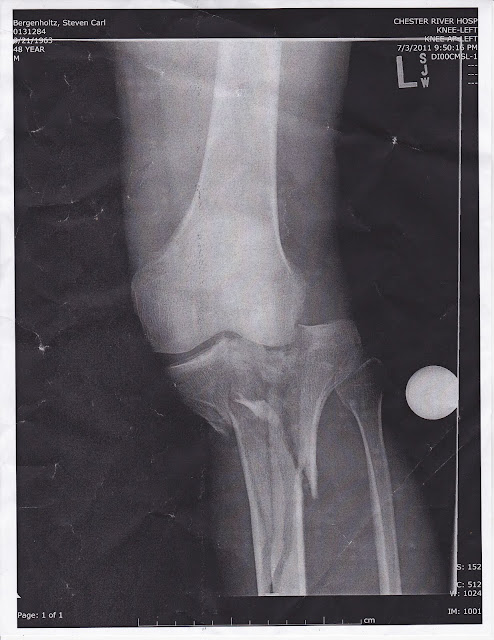

The surgeon said that the break is so severe that it is one typically seen in a motorcycle accident or similar high impact accident. We were initially worried that if the swelling didn't go down, they would have complete another surgery on his leg to reduce the pressure on the muscles. This would leave a gap in the skin and he would have to stay in the hospital to keep it sterile. If the swelling didn't go down at that point, he would have to stay in the hospital and get skin grafting. We were blessed that this worse case scenario did not come to pass. By Wednesday, we had hoped that he would be able to come home, but a reaction to the pain medication delayed his arrival home. Meanwhile, here at home, good friends (here in Maryland) offered rides and help and gave us things we needed for our comfort. They gave of their time and effort, bringing us an air conditioner, helping us move the king bed downstairs and bringing us groceries, since I cannot drive. He finally came home Thursday evening and we were all so glad to see him. There was nothing more beautiful than seeing him again!